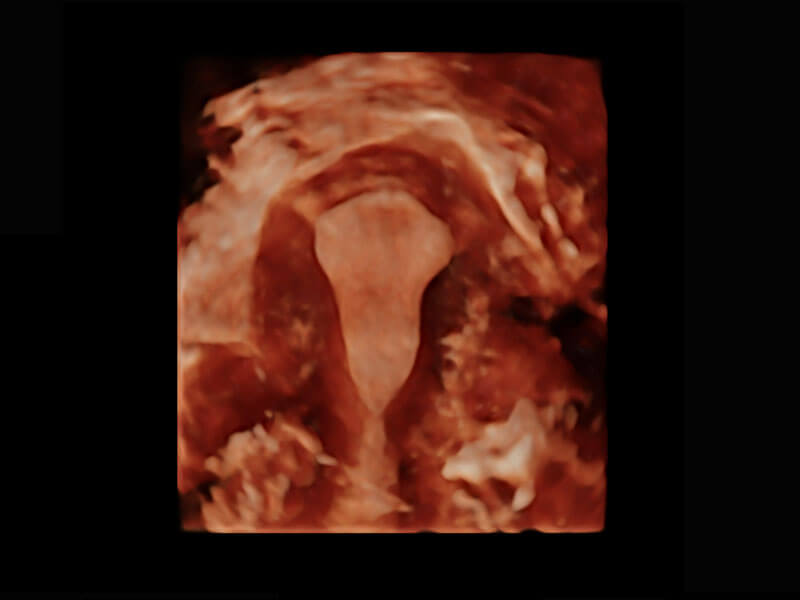

腔内三维-宫内节育器

腔内三维-光影成像